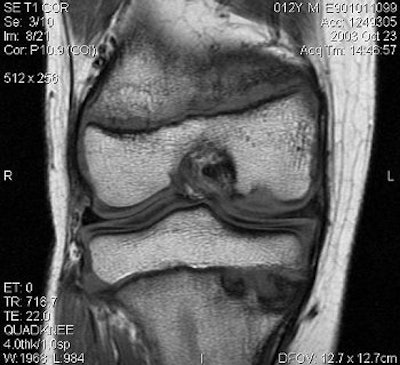

|  |

| JOCD of the capitellum. Coronal T2-weighted image (A, above), sagittal T1-weighted image (B, middle) and coronal T1-weighted image with fat saturation (C, below) demonstrate disruption of the articular cartilage (black arrows in images figures A and C) and the crescentic subchondral signal abnormality (white arrows in figures A and C) that is typical of an osteochondritis dissecans lesion. Images courtesy of Dr. Douglas Beall. |